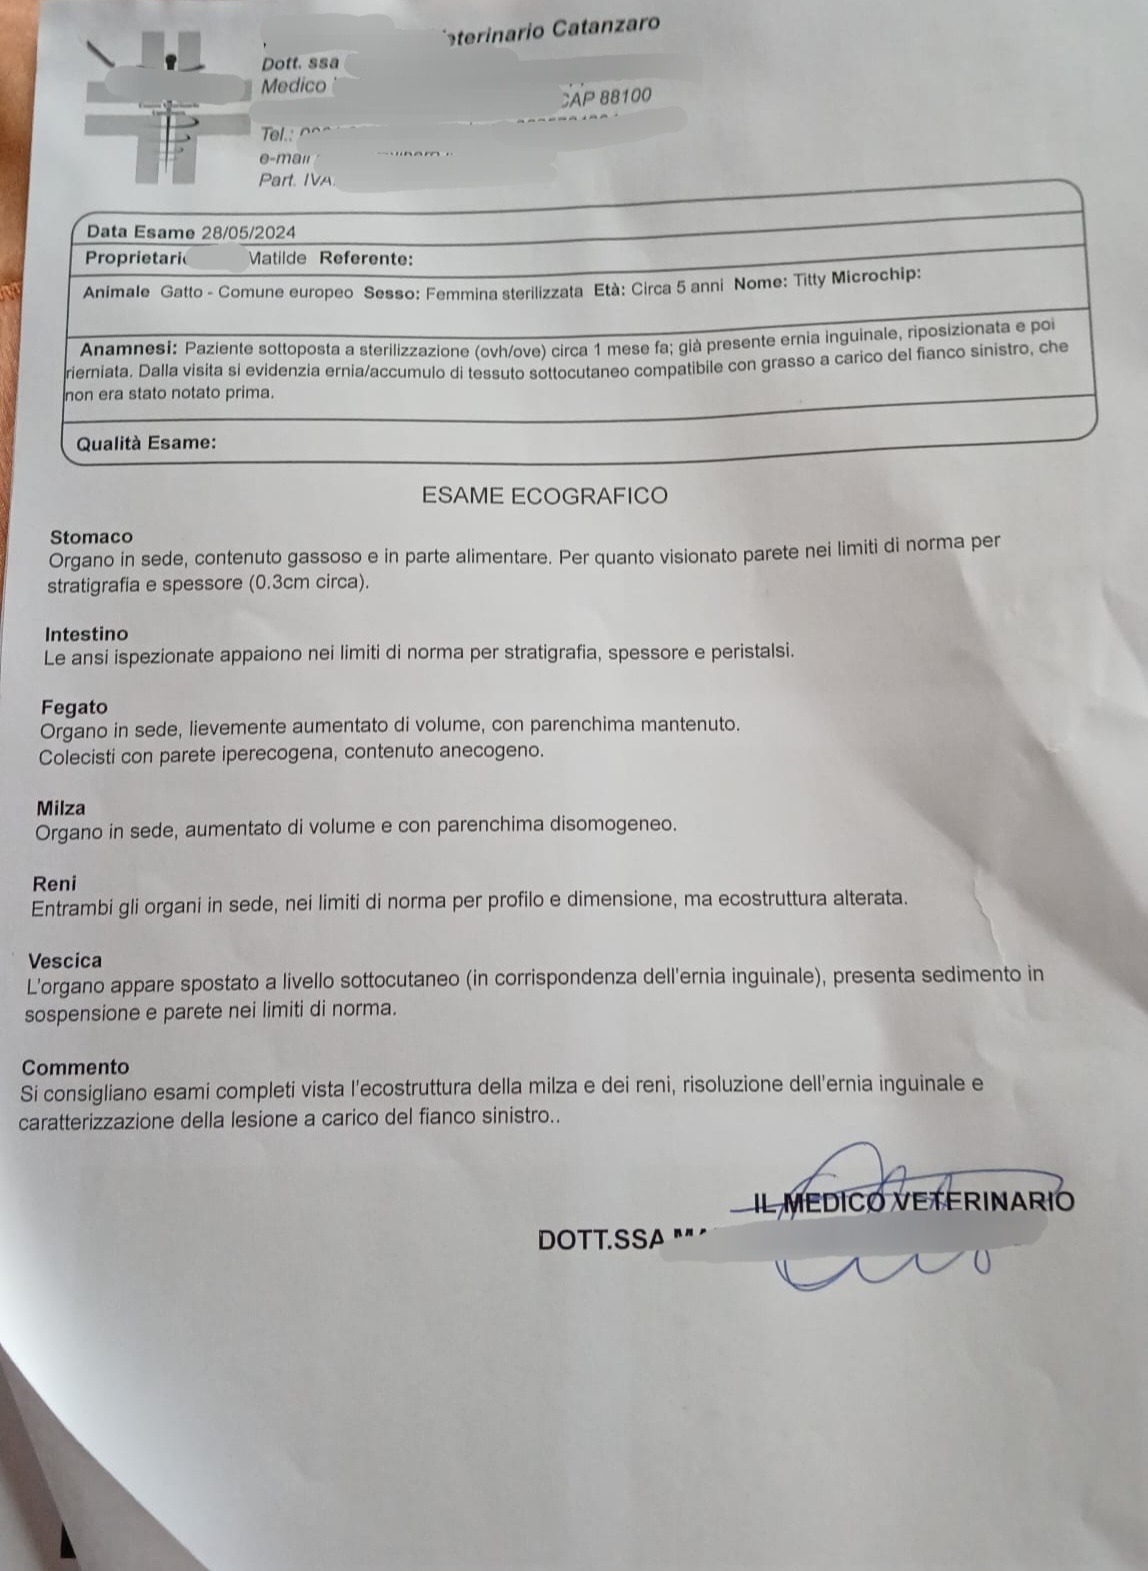

Sono stati fatti un sacco di esami ed eco, tra cui è risultata Positiva alla fiv, è stata prontamente sterilizzata dalla sua tata Ilde, ma purtroppo le disgrazie non finiscono qui, Titty ha un'ernia che va operata con urgenza, il costo dell'intervento più esami e degenza è quello che vedete nel preventivo, abbiamo bisogno di una mano per le spese